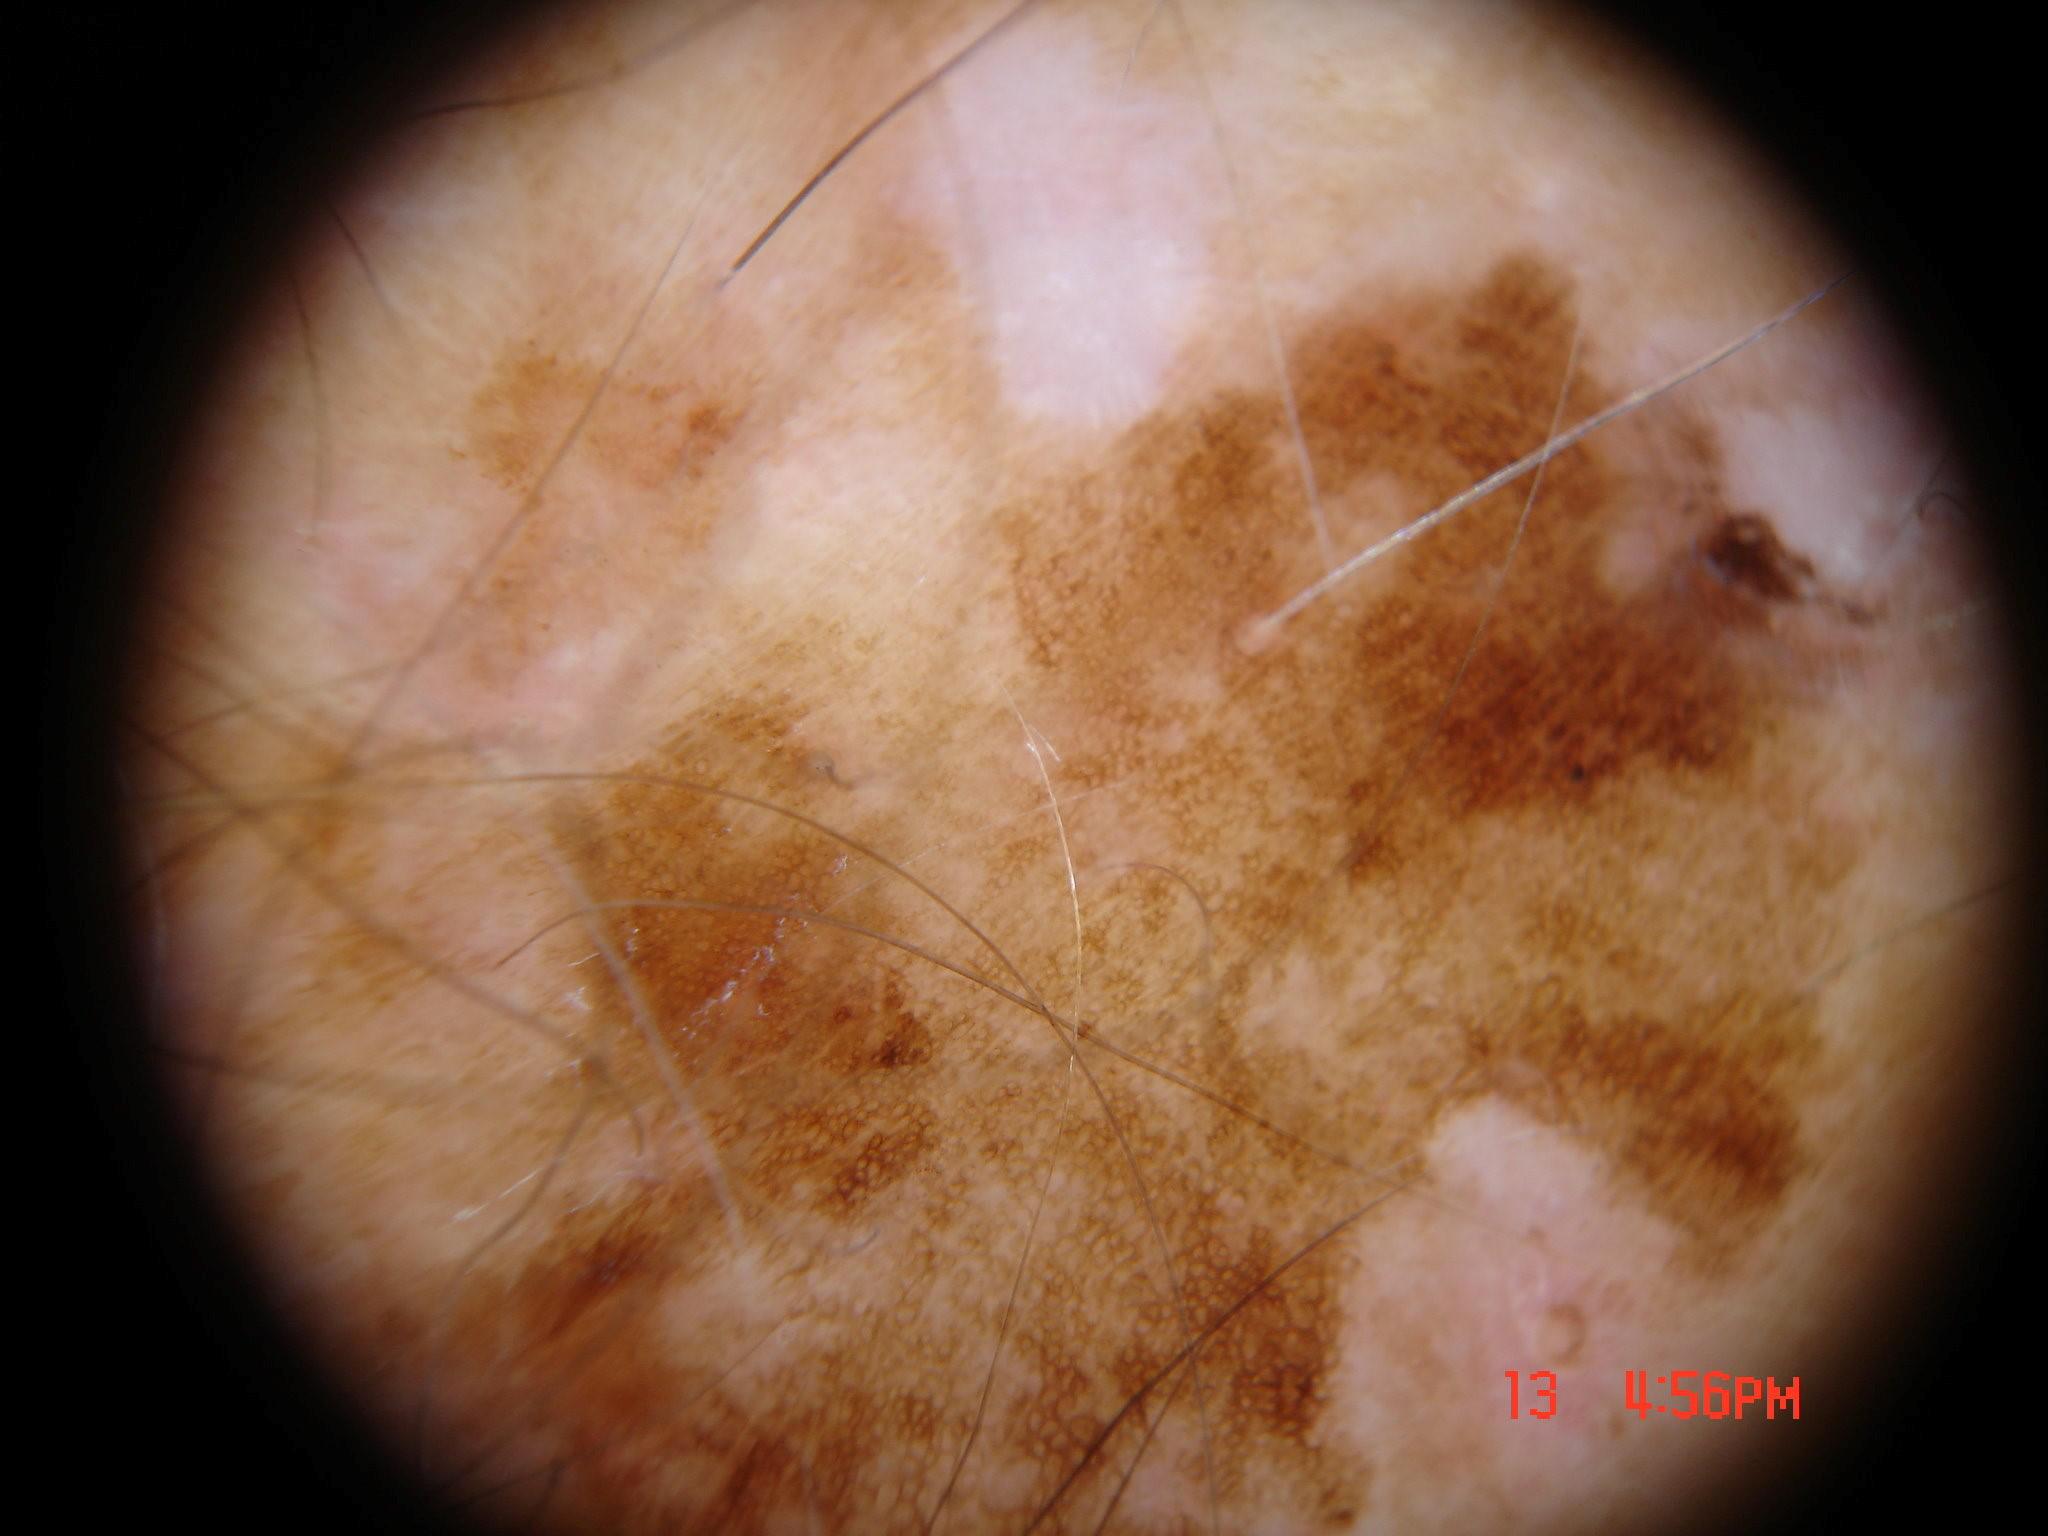

{

"age_approx": 50,

"anatom_site_general": "upper extremity",

"concomitant_biopsy": false,

"dermoscopic_type": "contact non-polarized",

"diagnosis_1": "Benign",

"diagnosis_2": "Benign melanocytic proliferations",

"diagnosis_3": "Nevus",

"diagnosis_4": "Nevus, Congenital",

"diagnosis_confirm_type": "single image expert consensus",

"family_hx_mm": false,

"image_type": "dermoscopic",

"melanocytic": true,

"patient_id": "IP_5994701",

"personal_hx_mm": true,

"sex": "male"

}